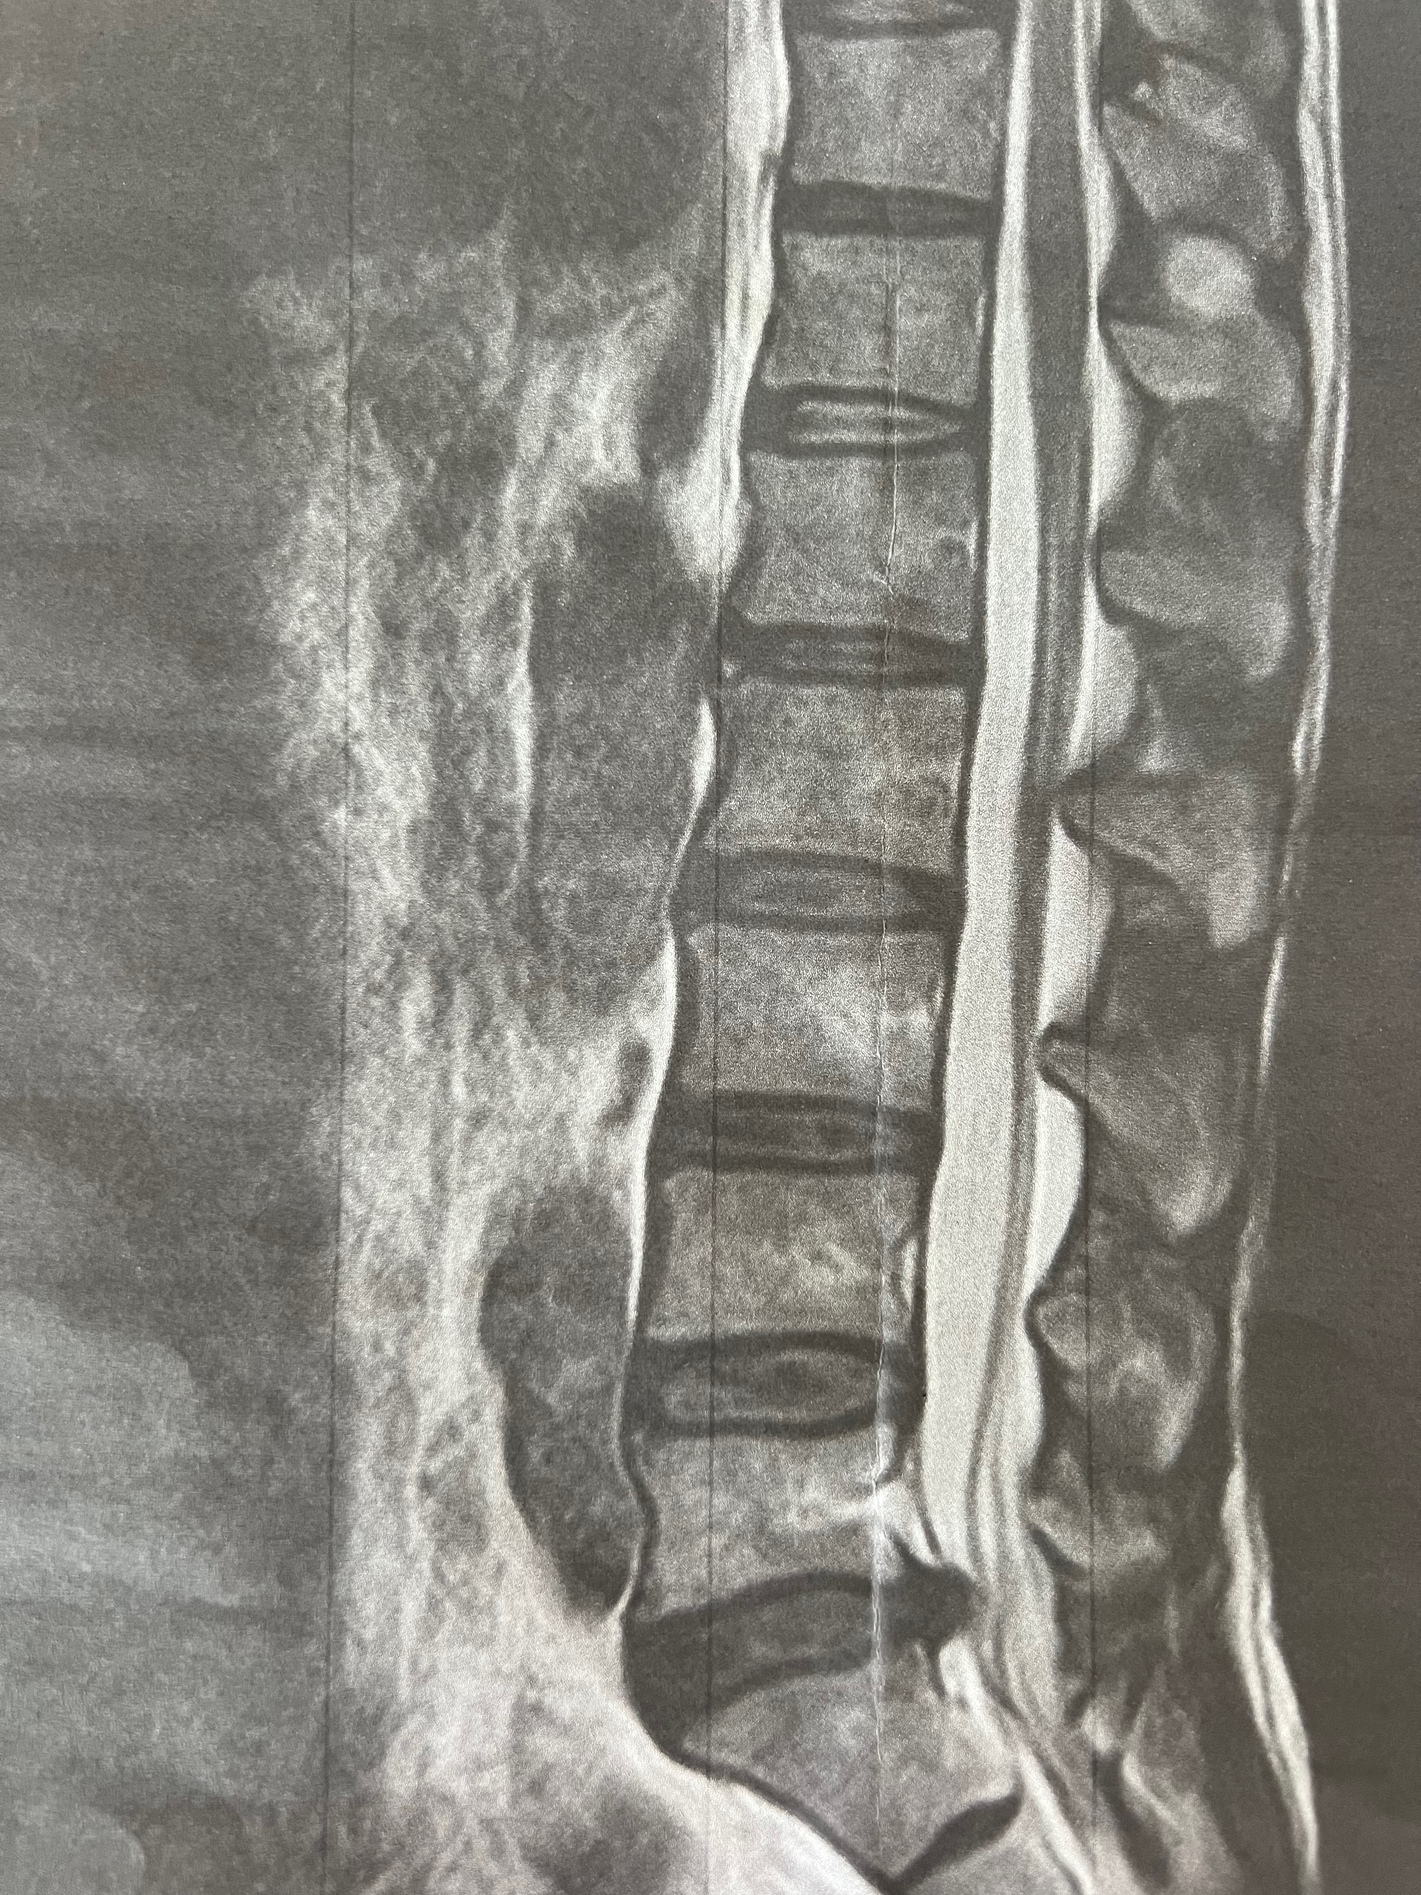

10/2。2、3日前に前回同様きっかけ不明のぎっくり風症状が再発したので、MRIやってくれそうなところに行ってみた。ヘルニア確定。これは手術すか?と聞いたところ、昨今は保存治療が基本だそうで、とりあえず3ヶ月様子見。最初の整形外科での非ヘルニア診断により初動をかなり誤った感じ。ちなみにギックリ風が出るとそっちがよりキツいせいか、坐骨神経痛症状が軽減する。